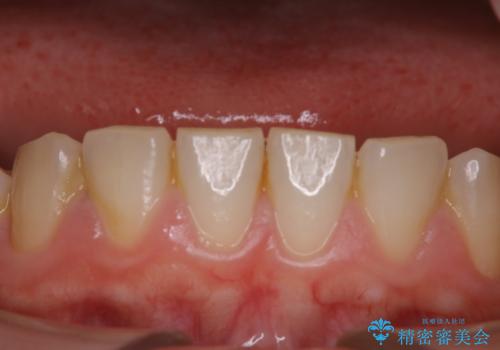

PMTCでコーヒーによる着色を除去。

- コーヒーを毎日飲むため、歯の表面についた着色をとりたいと来院されました。

歯の着色だけでなく、汚れもとれ歯の表面がツルツルになったと

喜んでいただけました。